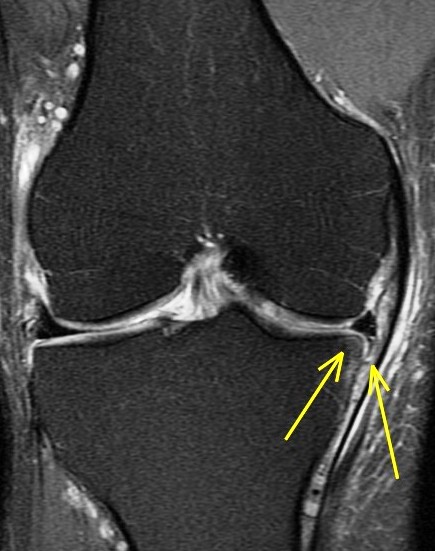

44 y/o male recreational runner. 2 week history of medial pain. r/o mmt.

Bone marrow edema is the radiologists friend. The posterior horn tear is easy to see. The displaced meniscus flap into the coronary recess adjacent to the body of the meniscus isnt so easy to see. The presence of bone marrow edema should alert us to the possibility of adjacent pathology leading to the reactive changes in the bone.

Unstable displaced medial meniscus tear( RID2772 ) with reactive tibial edema